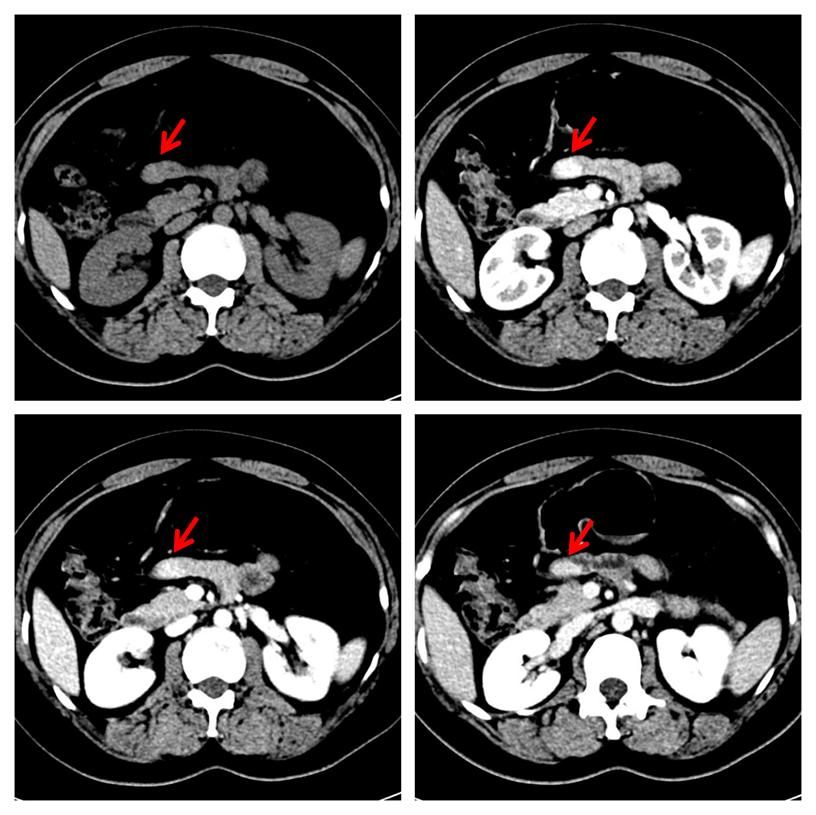

中年女性,2年前因"右胸壁惡性黑色素瘤"行手術(shù)治療,平素?zé)o腹脹、腹痛、惡心、嘔吐等不適癥狀。本次常規(guī)復(fù)查,行增強(qiáng)CT檢查發(fā)現(xiàn)小腸結(jié)節(jié),考慮神經(jīng)內(nèi)分泌腫瘤可能大(圖1)。本次發(fā)病以來,精神、飲食、睡眠差,近2 日有少量便血,小便無異常。體格檢查:腹部平坦,未見腸型及蠕動波,腹肌軟,無壓痛及反跳痛,腸鳴音弱。實驗室檢查:消化道腫瘤標(biāo)志物(甲胎蛋白、癌胚抗原、糖類抗原19-9、糖類抗原72-4)、血常規(guī)、肝腎功能均在正常范圍內(nèi)。

圖1,增強(qiáng)CT檢查示小腸結(jié)節(jié)(紅箭),明顯強(qiáng)化